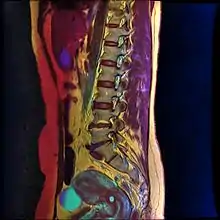

Nabothian cysts are also incidentally found during MRI imaging. During the healing process of chronic cervicitis, squamous epithelium of ectocervix proliferates and enter the cervical canal (endocervix), covering and obstructing the columnar epithelium of endocervical glands. Thus, retention of mucus in the endocervical glands causes cyst formation. The size of the cyst may vary from a few millimetres to 4 cm in diameter.[3]

If a cyst has an unusual appearance, a colposcopy will be performed to rule out other diagnoses.[4] If the blood vessels are short, comma-like or corkscrew-shaped and bleed on contact, then the cyst may be a very rare mucin-producing carcinoma of the cervix.[4] Magnetic resonance imaging is used to distinguish cancer from the typical nabothian cyst.[4]

T1-weighted MRI imaging would show intermediate to high intensity while T2-weighted imaging would show high signal intensity. Findings of solid components separating multiple cysts would be suggestive of adenoma malignum (a form of cervical cancer).[3]